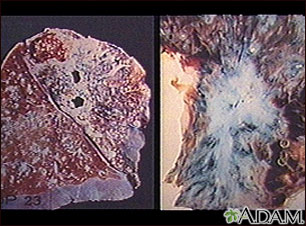

La tuberculosis es causada por un grupo de organismos:Mycobacterium tuberculosis, M. bovis, M. africanum y otros subtipos menos comunes. Por lo general infecta los pulmones, pero puede afectar otros órganos del cuerpo. Recientemente han aparecido cepas de tuberculosis resistentes a los antibióticos. Hoy en día, debido al número creciente de individuos inmunocomprometidos con SIDA, y de indigentes sin cuidado médico, los casos de tuberculosis han ido en aumento. (Cortesía de los Centros para el Control y la Prevención de Enfermedades -CDC- de los Estados Unidos)